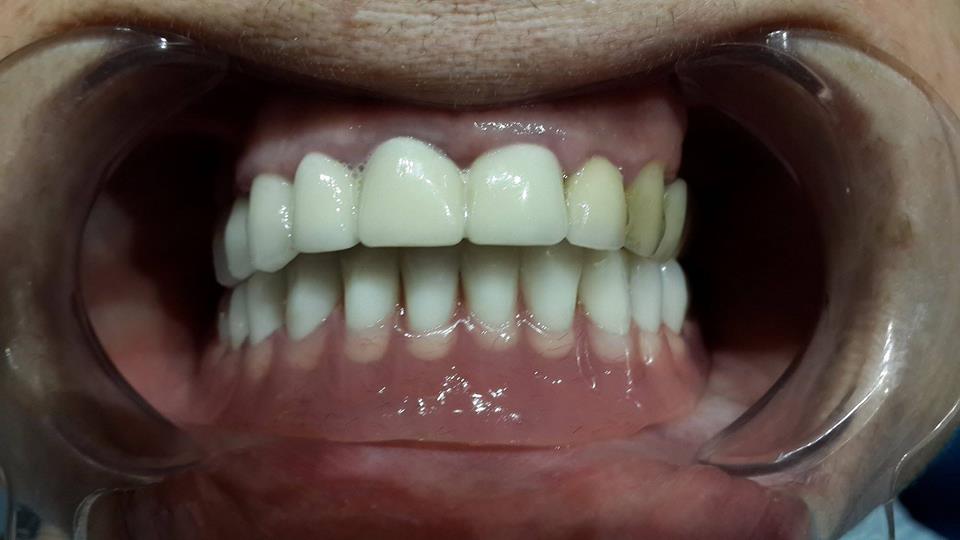

Prosthesis of the lower jaw on 4 implants

The patient was given a prosthetic lower jaw on 4 implants.